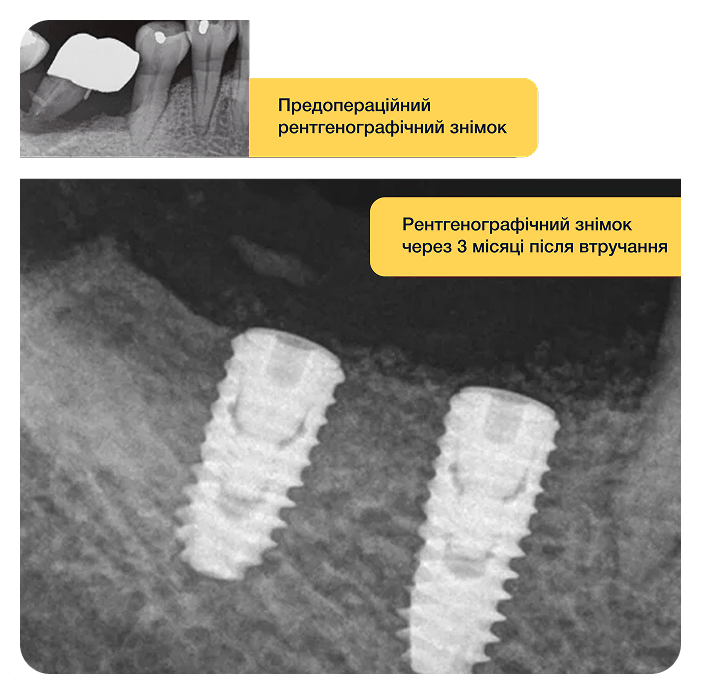

Ми не стверджуємо, що решта матеріалів на ринку погані. Але чи знаєте ви інший матеріал, який є джерелом власної гіалуронової кислоти пацієнта та відтворює кістку за 2-3 місяці?